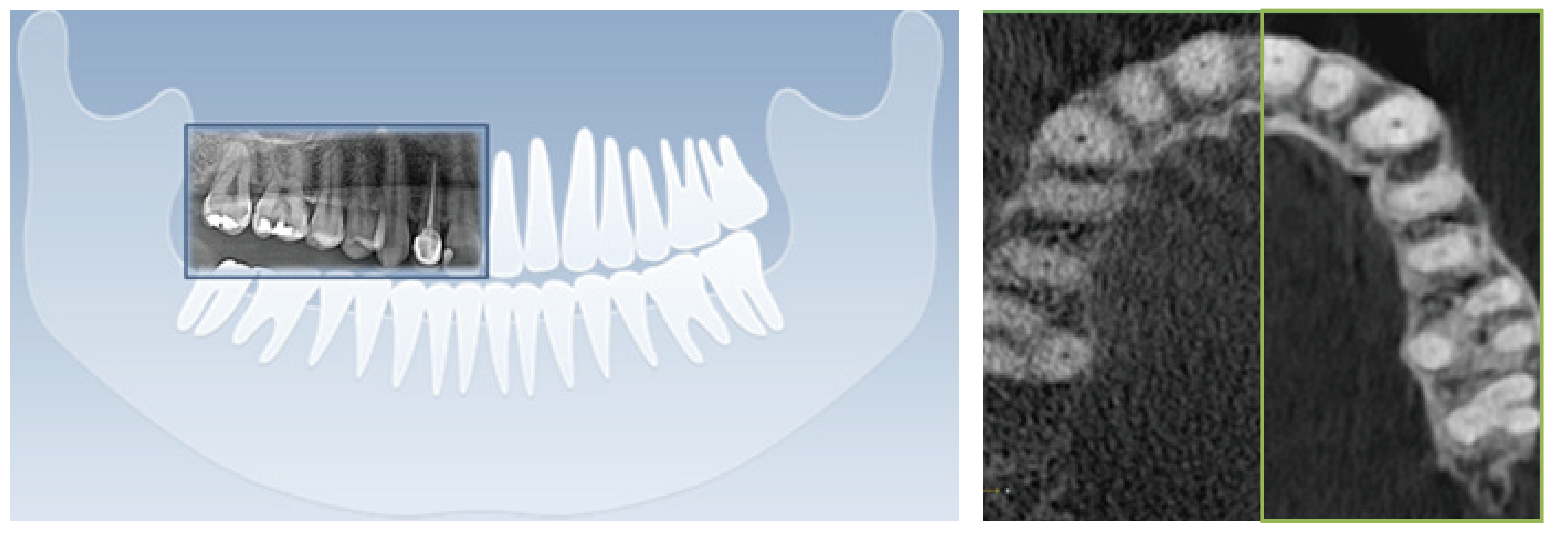

合理的噪點控制,造就精準的影像

低劑量,高質量

通過先進的工程學技術,低劑量的X射線也可以獲得高質量的圖像。

清晰的全景影像

通過多層技術,可以拍攝多張圖像,每張圖像被進一步分割。系統會自動選擇最佳焦點將其整合成一個優化的全景圖像。

前牙部畸變縮小,即使不單獨拍攝小牙片,也能準確診斷。清晰度可準確識別種植體螺紋和內部,確保連接程度和斷裂程度。